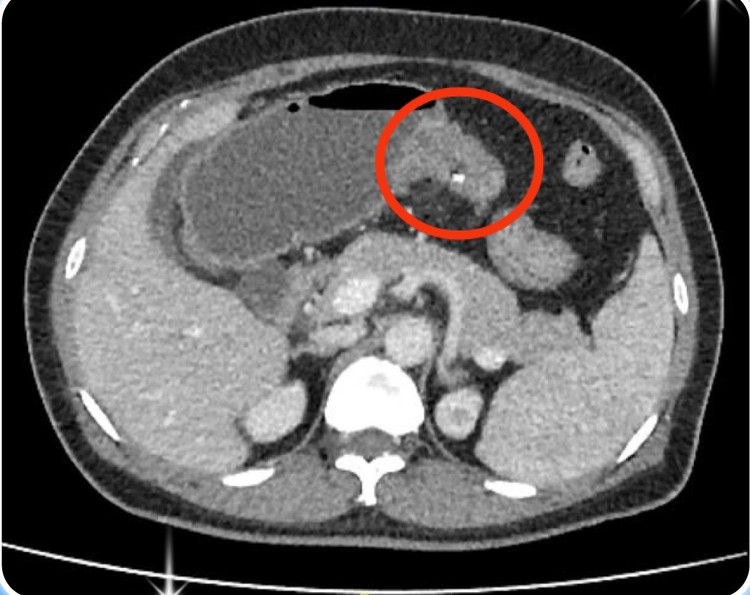

Tại phòng khám Ngoại tổng quát Bệnh viện Đa khoa Xuyên Á, bà T. được thăm khám và chụp CT-scan ổ bụng phát hiện có khối u đại tràng ngang, đây chính là nguyên nhân gây tắc ruột, chướng bụng. Các bác sĩ chỉ định bà T. nhập viện phẫu thuật.

Chia sẻ về ca phẫu thuật này, ThS.BS. Phan Trung Hiếu, khoa Ngoại tổng quát Bệnh viện Đa khoa Xuyên Á cho biết: “Trong giai đoạn cấp cứu tình trạng tắc ruột, chúng tôi tiến hành nội soi tiêu hóa đặt một ống thông chuyên biệt để giải áp đoạn đại tràng phía trên chỗ tắc, tránh tình trạng vỡ ruột.

| Hình ảnh CT khối u đại tràng - Ảnh BVCC |

Sau đó bệnh nhân sẽ được tiến hành hồi sức, bù nước dinh dưỡng để chuẩn bị tốt nhất cho một cuộc mổ cắt khối u. Sau một tuần đặt ống thông giải áp, ekip đã tiến hành mổ nội soi, cắt u và tái lặp lưu thông ruột. Chúng tôi ghi nhận ruột của bệnh nhân giảm phù nề nhiều, việc thực hiện miệng nối cũng dễ dàng, an toàn.